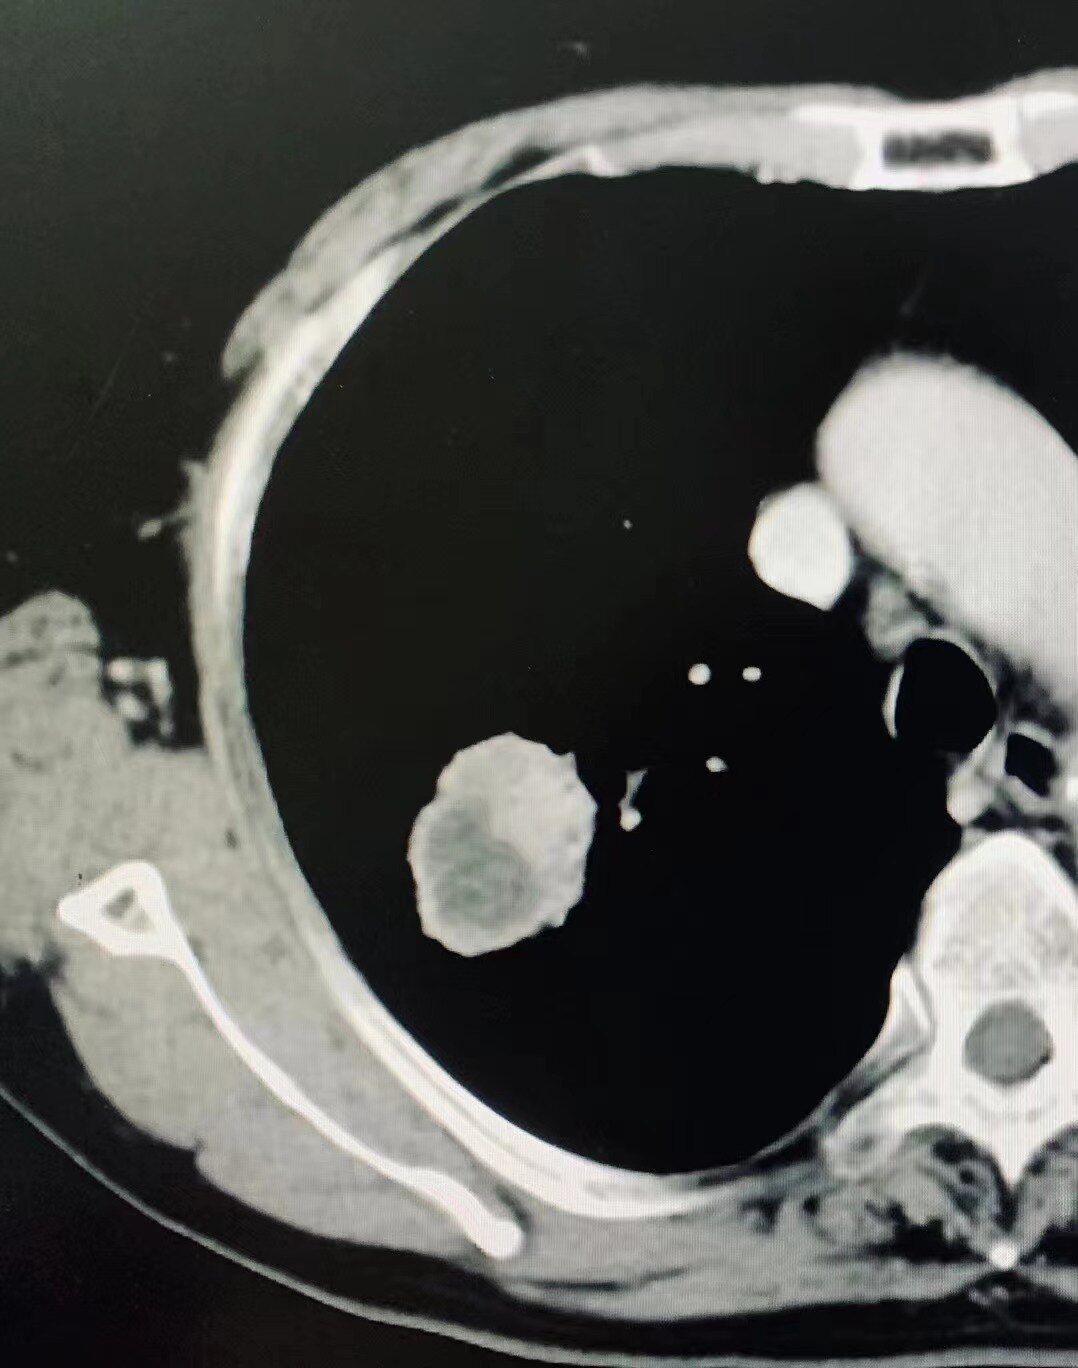

呼吸衰竭,连穿刺时都离不开氧气的W先生肺结节偏心坏死,有慢阻肺、广泛肺气肿,肺穿刺可谓不易!

杜学奎主任CT下肺穿刺

偏心坏死肿瘤